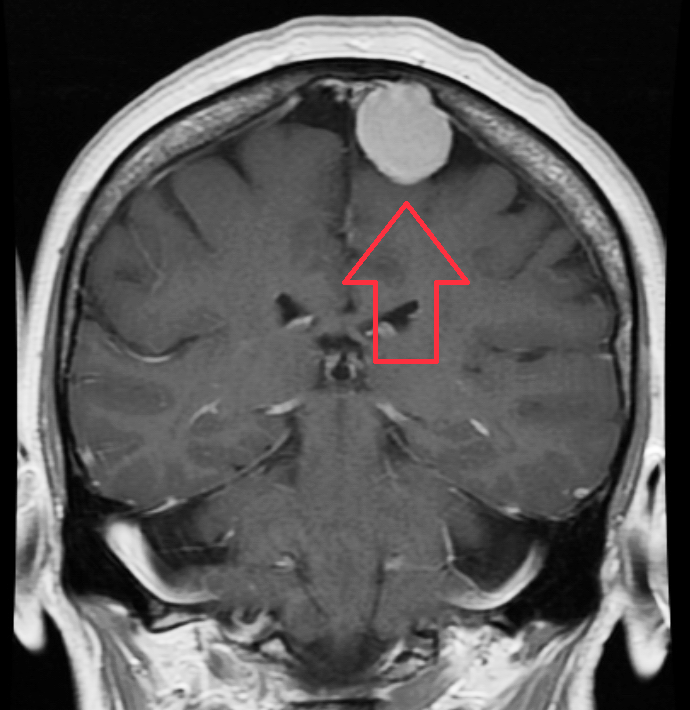

Meningioma

- Descrizione: Tumore nelle meningi.